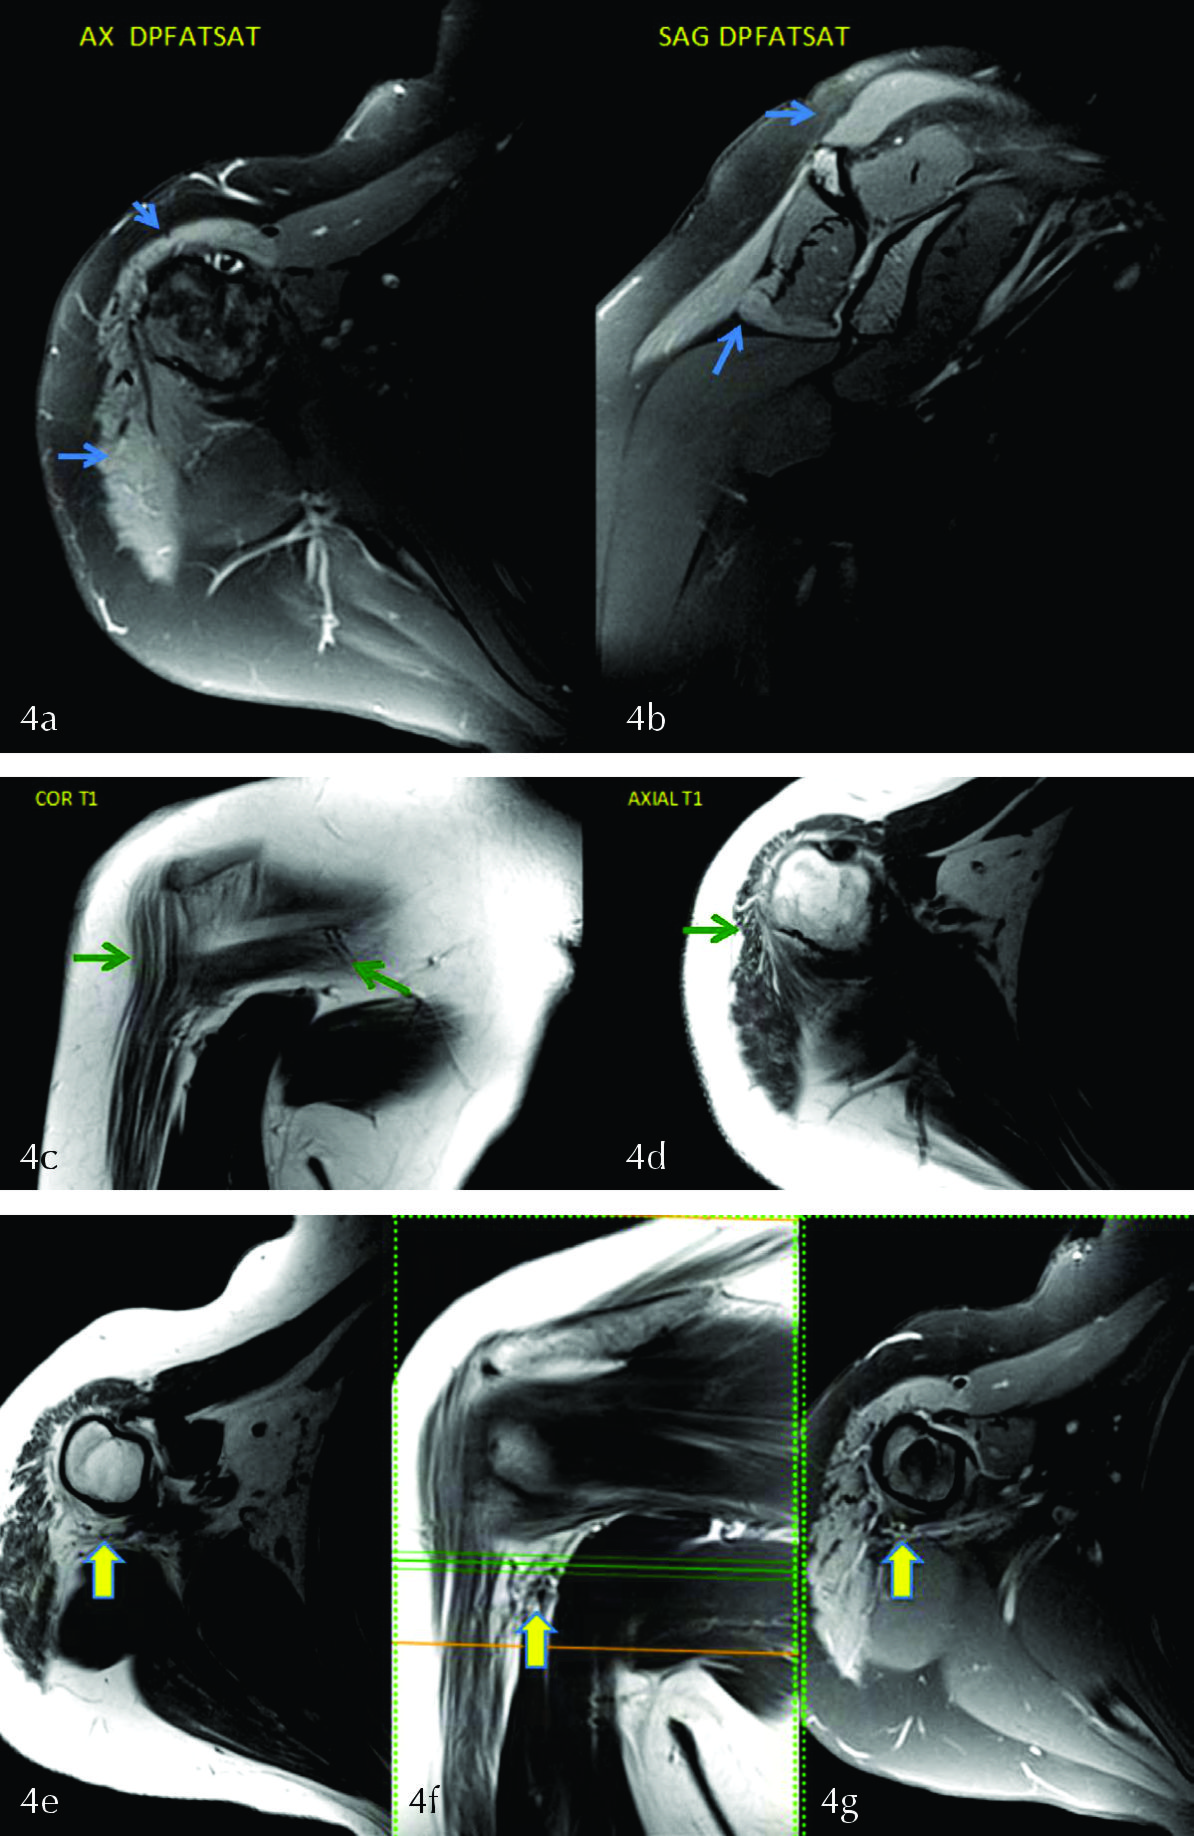

Paciente de 40 años, SF, a la que se le solicita una RM de hombro derecho con dato clínico de omalgia y antecedente de luxación de hombro. En las imágenes potenciadas en DPfatsat en los planos axial (fig. 4a) y sagital (fig. 4b) se visualiza hiperseñal en relación a edema en músculos deltoides y redondo menor. En las imágenes en secuencia T1 se observa pérdida de volumen e infiltración grasa por atrofia de los mismos (fig. 4 c y d). Estos hallazgos nos orientan a signos de denervación subaguda en territorio del nervio axilar.

El sitio de atrapamiento o lesión más frecuente del nervio Axilar es el espacio cuadrilateral, entre la diáfisis humeral, tríceps y redondo menor (fig. 4 e, f y g).

Si no se encuentra una causa compresiva en éste espacio se debe sospechar una lesión traumática post luxación, como en el caso presentado. La misma se puede ver hasta en el 45% de las luxaciones de hombro, por el desplazamiento de la cabeza humeral en la luxación misma o en maniobras de reducción (3,6,9).

Figura 4

En las imágenes DP FAT SAT en los planos axial y sagital (a y b) se evidencia edema en los músculos deltoides y redondo menor (flechas celestes). En las secuencias T1 coronal y axial (c y d) se visualizan signos de atrofia de los mismos músculos (flechas verdes). Imágenes axial y coronal T1 (e y f) y axial DPfatsat (g) delimitando el espacio cuadrilátero donde se encuentra el nervio axilar (flecha).